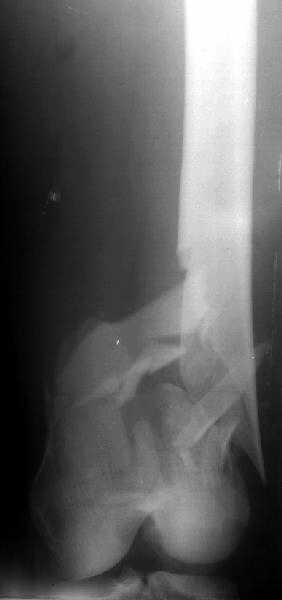

Отправитель: Abdelsalam Eid 28 Декабрь 2003, 19:30

I appreciate your admiration for Itramedullry nailin which you once told us was recently introduced in your unit.

But, don't you think you are using antigrade nails for some very low fractures including some intercondylar fractures. Do ou have a reference supporting antigrade nailing in such occasio in favour of other choices eg DCS, Supracondylar nail, condylar buttress plate. And perhaps you could show us also some of your results, that is (follow up) not immediate postop x rays.

Many thanks

1

2

de> you think you are using antigrade nails for some very low

de> fractures including some intercondylar fractures.

Exactly. It seems the option looks underestimated.